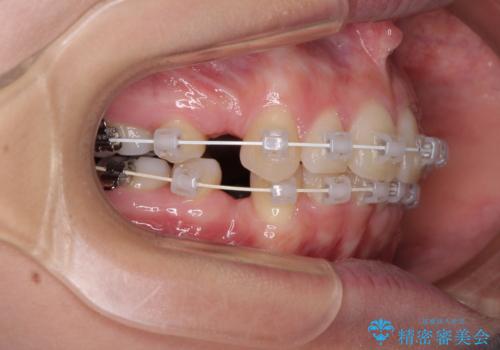

デコボコで飛び出した前歯 ワイヤー装置による抜歯矯正

- 上下前歯のデコボコと、飛び出した前歯を気にして来院された患者様です。

口元を積極的に引っ込めるために、上下左右の小臼歯計4本を抜歯することとしました。

咬み合わせが深く、咬合力強いため、補助装置を使用しながら積極的に口元を下げることとしました。

矯正治療前の咬み合わせで、前歯がすり減ってしまい、歯列が整ったときに先端がガタガタになってしまったため、矯正治療後に形態修正を行いました。